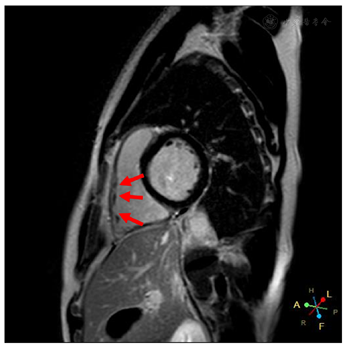

入院体格检查:体温36.4℃,脉搏70次/min,呼吸16次/min,血压110/70 mmHg(1 mmHg=0.133 kPa),神清、精神可,双侧瞳孔等大等圆,光反射灵敏,双肺呼吸音清,未及干湿啰音,心律齐,各瓣膜听诊区未闻及杂音,双下肢无水肿。心电图提示窦性心律,Brugada波Ⅱ型(图1),将V1、V2上移两个肋间复查心电图出现Brugada波穹窿型Ⅰ型(图2)。心脏超声右心室流出道远端稍增宽,右心室流出道近端内径27mm,远端内径31mm,左室功能和结构未见异常(图3)。心脏核磁显示右室心肌延迟增强,提示纤维化(图4)。冠状动脉CT血管成像(CTA)未见异常,直立倾斜试验阴性。

ARVC是由编码桥粒蛋白的基因突变引起心肌细胞间连接中断,心肌细胞坏死并被纤维脂肪组织替代。ARVC早期可单纯表现为起源于右心室的室性心律失常,晚期右心结构改变较突出,表现为右心室整体和局部扩张及功能障碍,伴明显的局部运动障碍。因此Brugada综合征与ARVC在突变基因型、有无明显的心肌病改变、心律失常的发生机制及预后方面均存在显著差异。本例患者心脏超声提示右室流出道增宽,核磁显示右室心肌纤维化,而基因检测无桥粒基因突变,心电图未发现Epsilon波,根据ARVC诊断标准(2010)专家共识的评分标准[6],本例患者尚不能诊断ARVC,但研究显示对于Brugada综合征伴有右心室结构异常的患者,发生室性心动过速风险更高,因此对于这类高危人群进一步随访尤为重要。

因此,有不明原因晕厥史的BrS患者,属于猝死高危人群,推荐植入ICD。心脏核磁能早期发现Brugada综合征是否合并右室结构和功能改变,基因检测能探究心脏基础病变,但临床实践中很难首先从基因检测开始进行诊断,医生更应重视临床表现、体征或辅助检查,对于KCNH2突变的Brugada综合征患者,药物治疗时应注意QT延长问题。